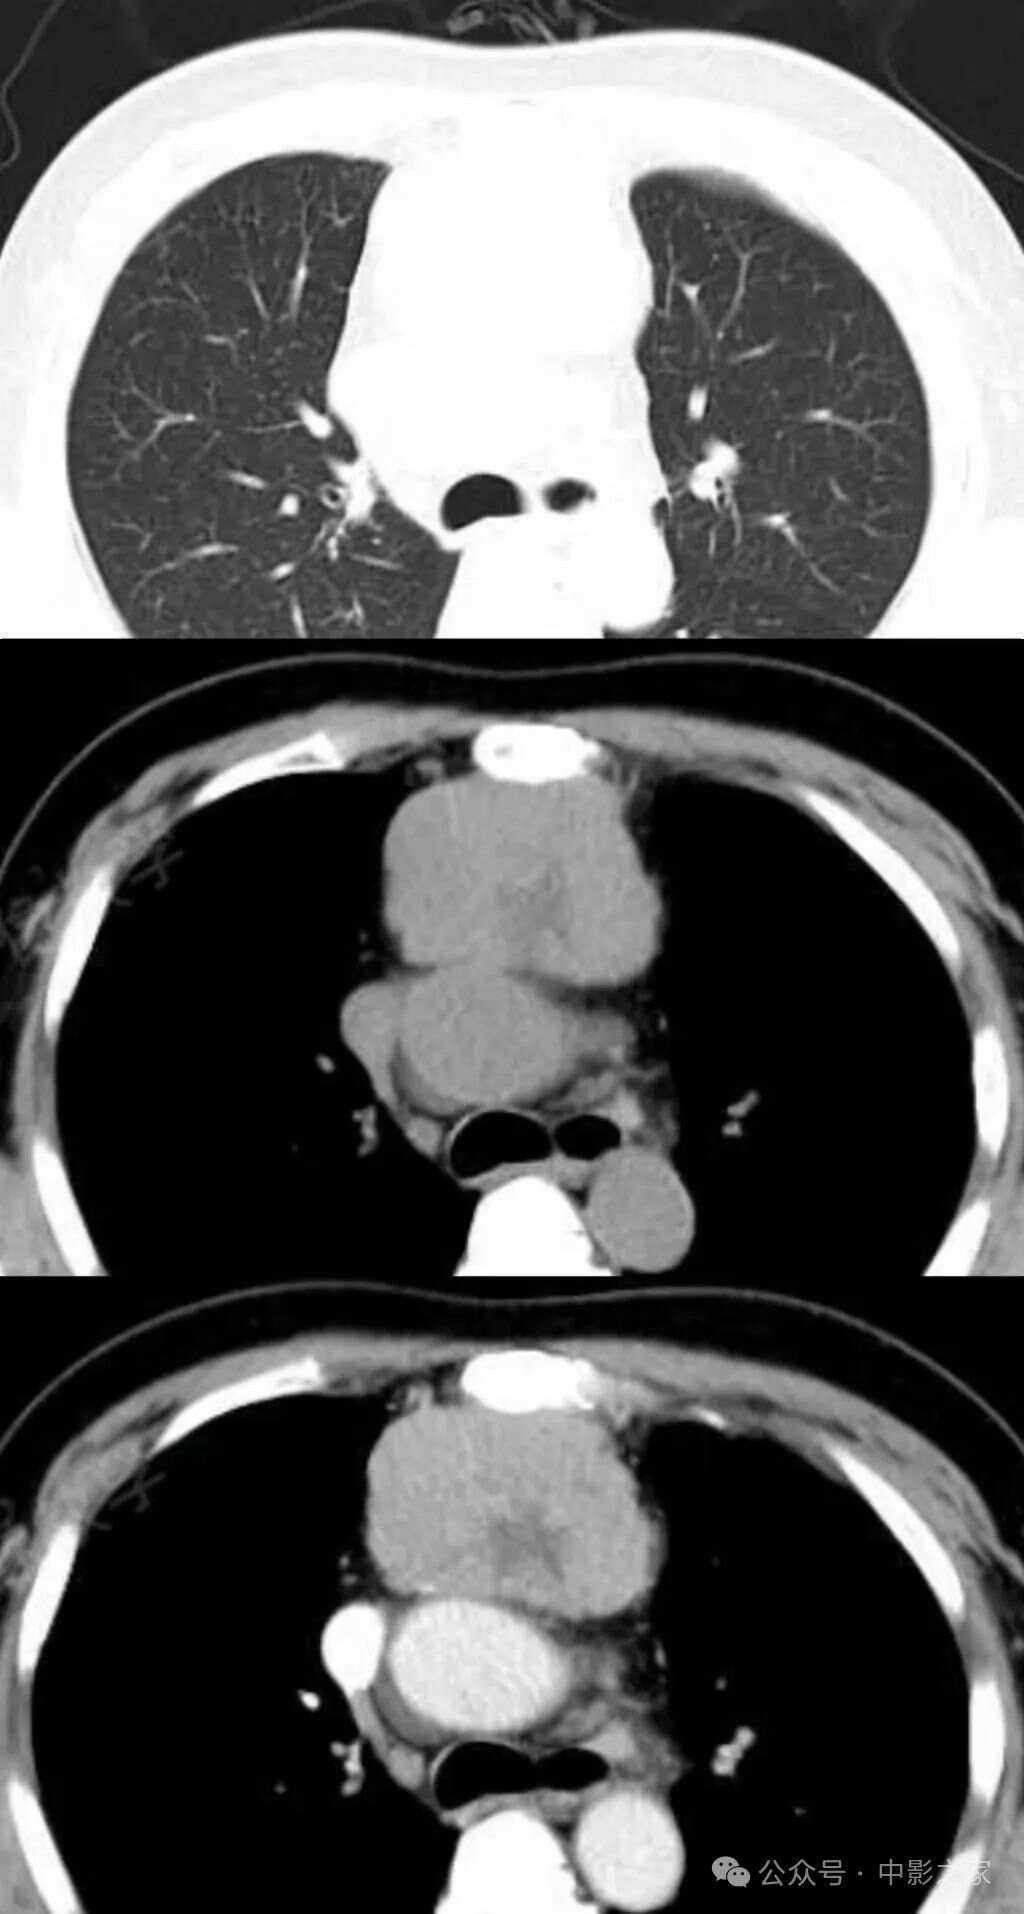

前纵隔占位是一个影像学诊断,通常提示在前纵隔位置存在占位性病变,大部分是纵隔肿瘤的可能性以下是关于前纵隔占位的详细解释定义前纵隔占位是指在CT或胸片检查中,发现前纵隔位置存在异常结构或肿块,占据了原本应有的空间常见病变胸腺瘤是前纵隔最常见的肿瘤之一,多为良性,但也有恶性可能;纵隔肿瘤密度是指肿瘤在影像学上显示的密度,是通过CT扫描或MRI等影像学技术测定得到的以下是关于纵隔肿瘤密度的详细解释密度类型纵隔肿瘤的密度分为高密度中等密度和低密度等多种类型这些密度的分类与肿瘤的组织成分血供情况和坏死率等因素有关密度意义高密度通常意味着肿瘤细胞的组织密度;纵隔上抬是指胸腔内的纵隔组织受到压迫而上升的现象患有心血管疾病肺部疾病或纵隔肿瘤的患者可能会出现纵隔上抬的症状通常情况下,这种症状会引起呼吸困难和胸痛等不适感,给患者带来严重的身体和心理负担因此,及早发现并治疗纵隔上抬的症状,对保障患者身体健康和生命安全具有重要作用纵隔上抬的。

纵隔肿物是指在纵隔范围内生长出来的新生物,可以出现在前纵隔中纵隔或后纵隔这些肿物可以是实性的囊性的,也可以是良性的恶性的或交界恶性的纵隔肿物的类型纵隔肿瘤是一个广泛的疾病系列,包括多种不同细胞类型的恶性肿瘤还包括在发育过程中出现的良性疾病,如支气管囊肿食管囊肿和肠源性囊肿前纵隔肿物可能包括胸腺增生胸腺退化。